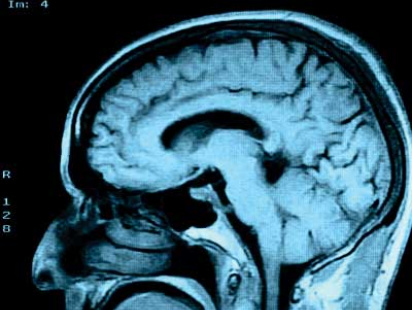

Brain networks differ among those with severe schizophrenia

People with a severe form of schizophrenia have major differences in their brain networks compared to others with schizophrenia, bipolar disorder and healthy individuals, a new study from the Centre for Addiction and Mental Health (CAMH) shows.

The study, which used a novel approach to map brain networks, was led by researchers at the Campbell Family Mental Health Research Institute at CAMH and published in this week's JAMA Psychiatry.

The study involved magnetic resonance brain imaging (MRI) with 128 people with schizophrenia and 130 healthy individuals at two sites, and with 39 patients with bipolar disorder and 43 healthy individuals at a third site. Patients with bipolar disorder also experience psychotic symptoms but not negative symptoms, so these patients served as an additional comparison group. The three sites were at CAMH, the Zucker Hillside Hospital in Glen Oaks, New York, and the Central Institute of Mental Health in Mannheim, Germany.